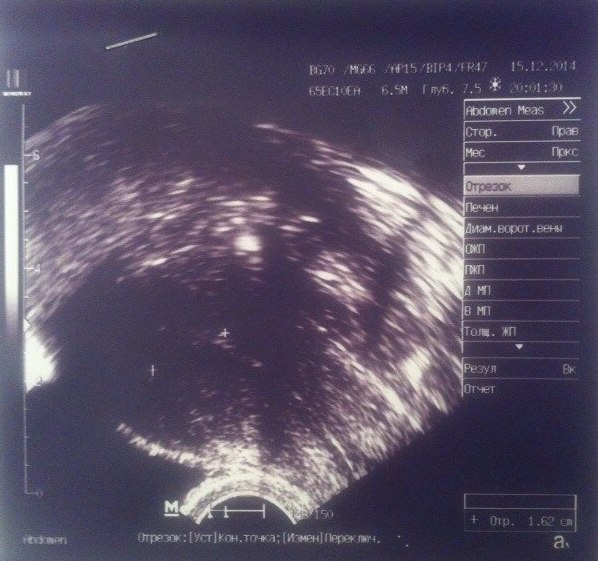

Фолликулометрия 11 ДЦ

Не понимаю как но я дошла до узи и получила консультацию врача. Прошу под кат Первое что меня приятно удивило так это то что врач ОН. Я всегда считала что мужчины лучше девушек (сори). Эндометрий ну ооочень тоненький 4 мм. ДФ в этот раз в ЛЯ 16*14, к 14-ому ДЦ должен созреть и лопнуть. Что касается моих гормонов ЛГ, ФСГ,Пролактин он сказал что очень даже все хорошо, НО если овуляция сама не произойдет будем наращивать эндометрий. Примерно так:

и конечно же мои снимки